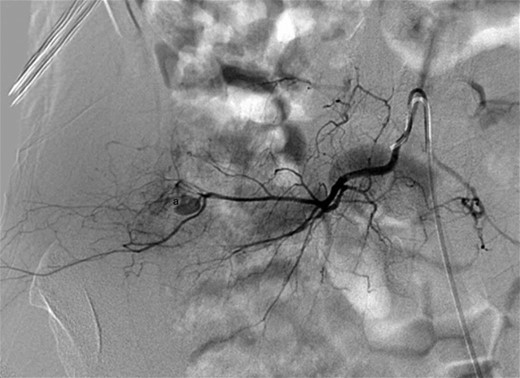

Digital subtraction angiography showing a small pseudoaneurysm originating from the peripheral aspect of the distal right lumbar artery (a).